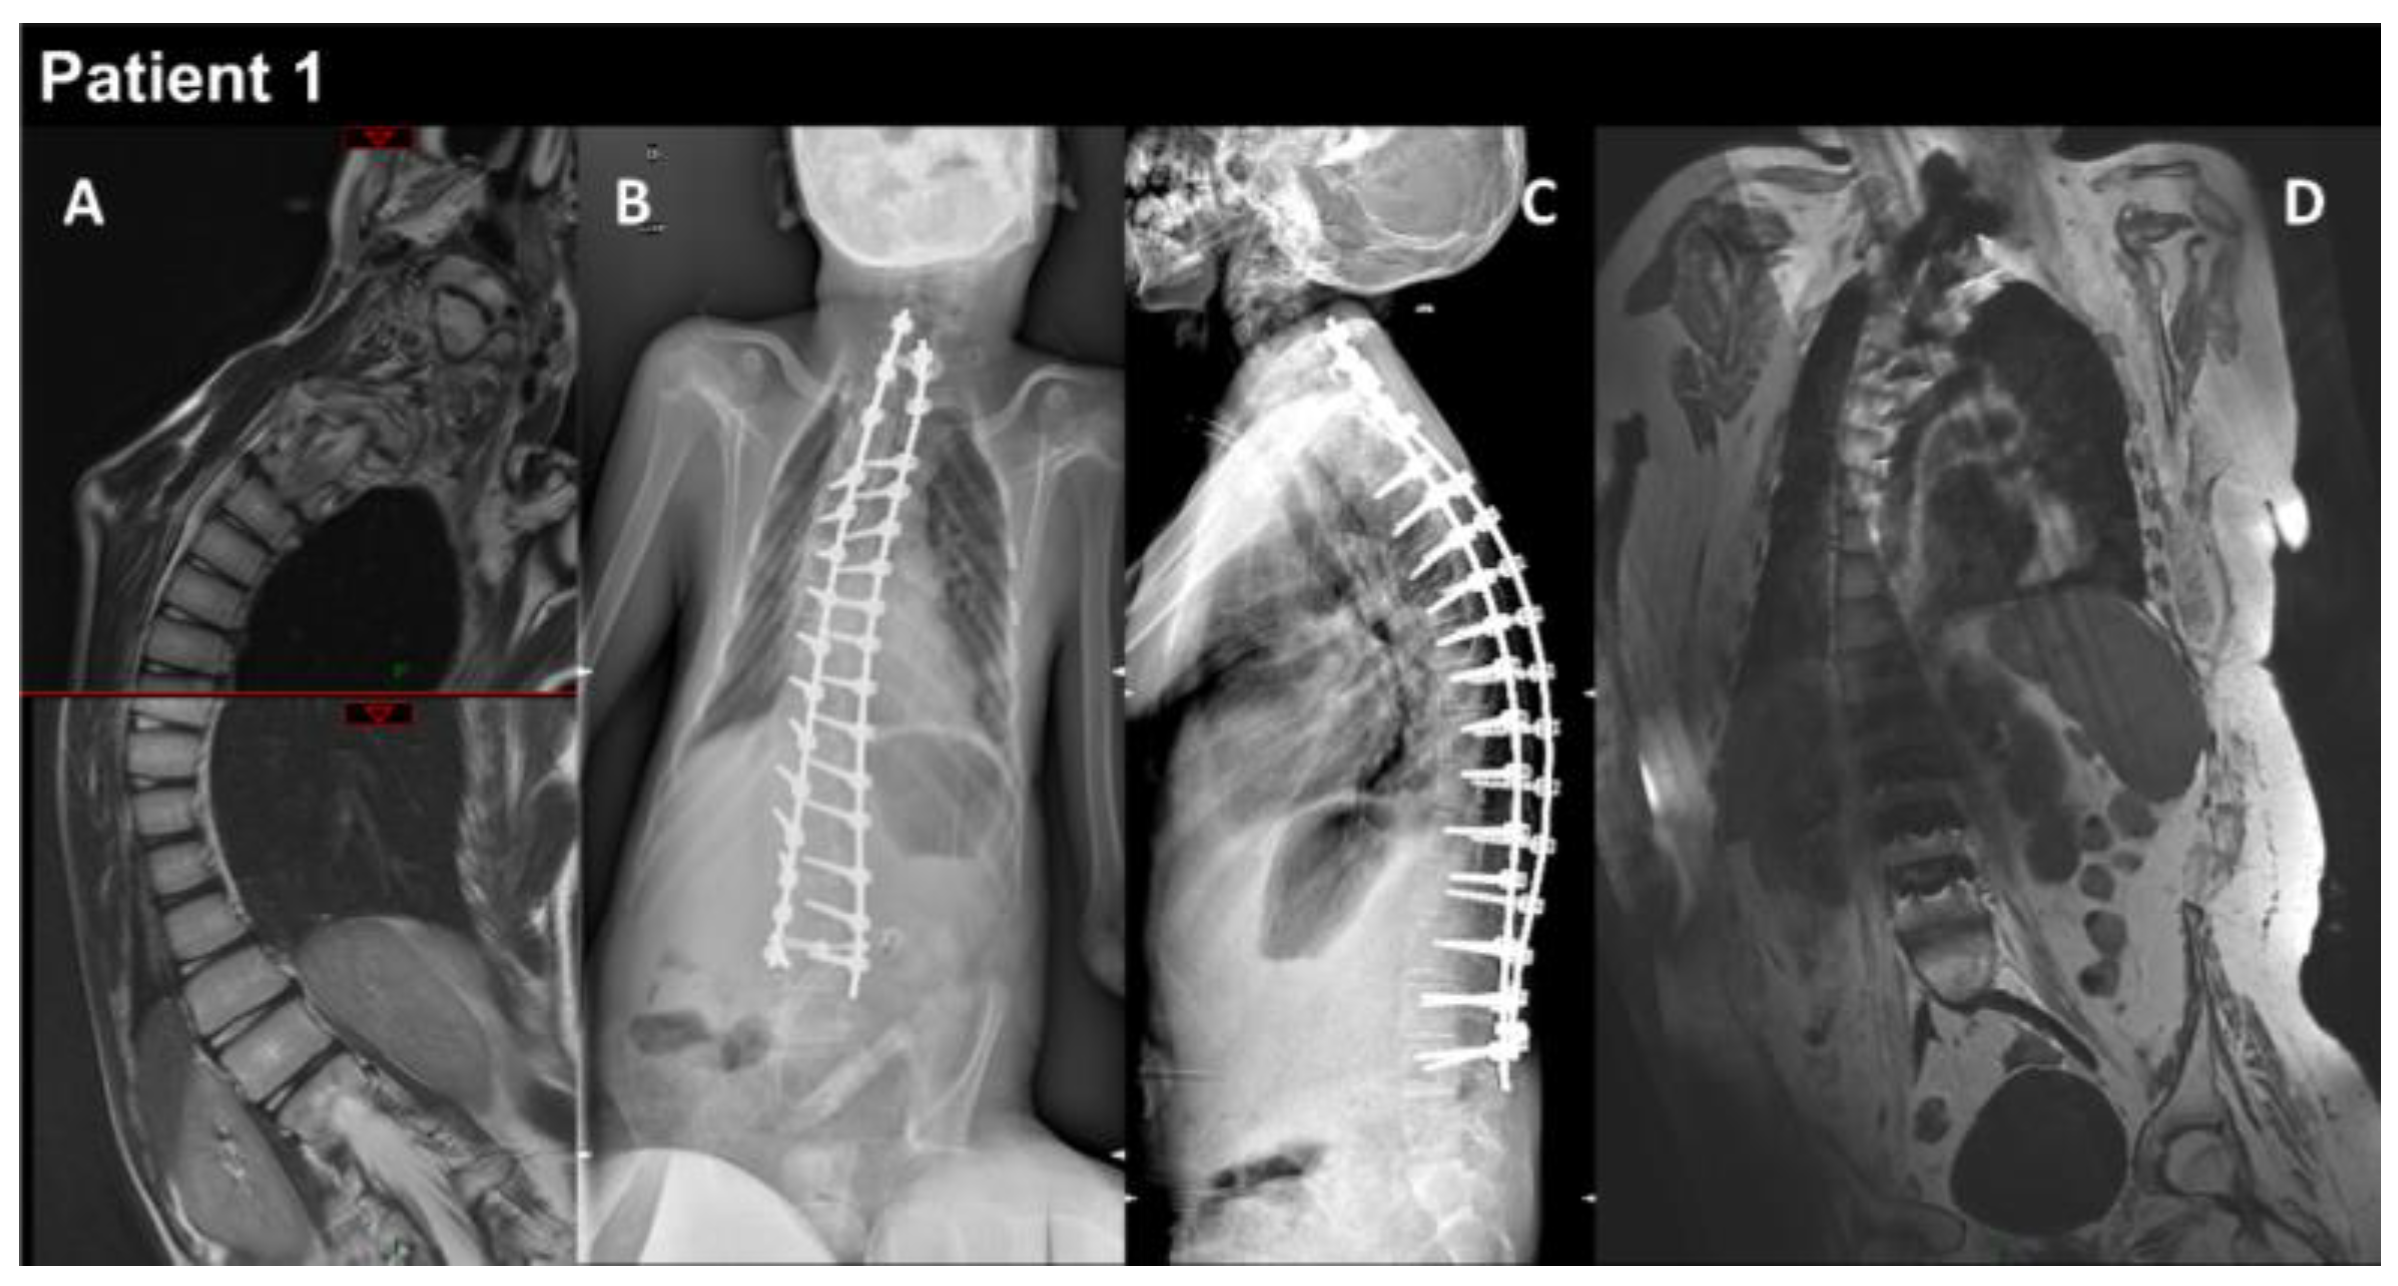

| THIS STUDY | P1 | M | heteroz., de novo | RCM + myopathy | Birth | 13 y | Global | Yes | Yes | Myopathic | Normal | RCM | Restrictive respiratory syndrome | Alive at 17 y | Yes |

| P2 | M | heteroz. | HCM + myopathy | 2 y | 39 y | Global | - | Yes | - | Increased | HCM | Restrictive respiratory syndrome | Alive at 43 y | Yes | |